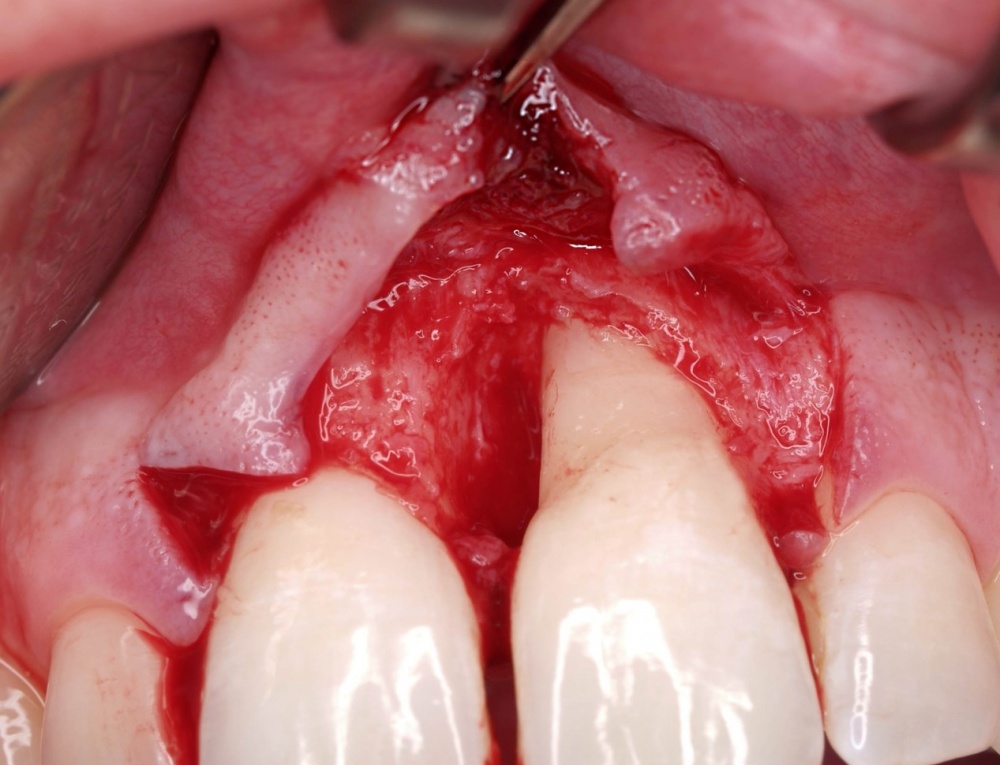

Die Berührungspunkte der Zahnmedizin mit der Inneren Medizin sind ein Paradebeispiel dafür, dass die Mundhöhle eben nicht als ein isolierter Bereich gesehen, sondern mit dem Organismus insgesamt beurteilt werden muss. Beispielhaft dafür seien hier einige systemische Erkrankungen wie die Arteriosklerose, der Diabetes mellitus oder respiratorische Erkrankungen erwähnt. Der Hauptgrund für diese fachliche Nähe ist die Parodontitis, die zumeist chronische Entzündung des Zahnhalteapparats (Abb. 1). Sie weist eine hohe Prävalenz auf und stellt die häufigste chronische Erkrankung im gesamten Organismus dar. Unterschiedliche Verlaufsformen und klinische Schweregrade werden unterschieden. In den allermeisten Fällen ist eine Vielzahl von Parodontien pro Individuum betroffen, sodass daraus in der Summation ein großflächiges Entzündungsareal bis hin zur Größe einer Handinnenfläche (ca. 70 cm²) resultiert. Interaktionen zwischen dem Organismus und dem Parodont sind belegt und legen die Vermutung nahe, dass eine Parodontitis ihrerseits Auswirkungen auf mögliche Erkrankungen des Organismus haben könnte. Durch die Infektion des Parodonts können Bakterien und ihre Stoffwechselprodukte in den Kreislauf gelangen, ihrerseits dann im Organismus allgemeine Erkrankungen hervorrufen, ungünstig beeinflussen oder zu Sekundärreaktionen führen. So sei beispielhaft erwähnt, dass in chirurgisch entfernten arteriosklerotisch veränderten Gefäßanteilen parodontal-pathogene Keime in teilweise hohen Konzentrationen nachgewiesen wurden, während in gesunden Arterien diese Keime nicht nachgewiesen werden konnten. Mittlerweile mehren sich auch Hinweise darauf, dass es zwischen der Parodontitis und dem Diabetes mellitus ebenfalls eine wechselseitige Beziehung gibt. So war die Mortalität bei Diabetikern mit profunder Parodontitis um das Zweifache erhöht. Weiterhin konnte in anderen Studien der Einfluss der Parodontitis auf den Blutzuckerspiegel belegt werden. Interessant ist in diesem Zusammenhang natürlich die Frage, ob die Parodontaltherapie selbst einen positiven Effekt auf den Blutzuckerspiegel hat. Die zu dieser Fragestellung durchgeführten Forschungen brachten noch keine eindeutigen Ergebnisse. Gleichwohl konnte in verschiedenen Studien mittels einer Parodontaltherapie ein positiver Effekt auf den Blutzuckerspiegel erzielt werden. Auf viele ätiologische Aspekte kann in diesem Rahmen nicht näher eingegangen werden. Die genannten Beispiele mögen jedoch belegen, dass es zwischen der Inneren Medizin und der Zahnmedizin viele „gemeinsame“ Patienten gibt, die eine enge Kooperation sinnvoll machen. Um diese zu verbessern, ist insbesondere eine Vermittlung der eben angesprochenen Erkenntnisse in einen möglichst großen Kollegenkreis anzustreben.